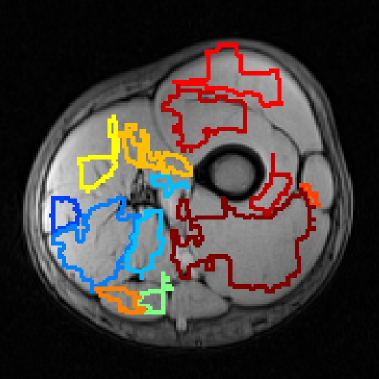

II-C Muscle labeling

A muscle atlas was defined using the same images involved in each cross-validation iteration. First, all images are registered to a common reference, selected randomly among the training set. Image registration relies on the convex hull of full set of muscle labels for each MRI slice and 2 key points - the bone centroid and the most distal point on the referred convex hull, with respect to the bone centroid.

One image is randomly selected as a reference for the atlas relative positioning among the training set. In the first step, bone centroids of reference and target MRI slices are aligned through translation.

Considering the translated images, let D1subscript𝐷1\vec{D_{1}} and D2subscript𝐷2\vec{D_{2}} be the vectors connecting the bone centroid to the most distal point along the convex hull of the muscle labels, in the reference and target images, respectively. Images are then further aligned using rotation by the angle between vectors D1subscript𝐷1\vec{D_{1}} and D2subscript𝐷2\vec{D_{2}}. Finally, considering the convex hull of the muscle labels in the reference image, the target images are scaled to match the reference.

After aligning the images within a common frame, a probability map is obtained for each muscle, overlapping the binary masks of all manually designed ROI with the same label (Figs. 2(a), 2(b) and 2(c)). The resulting topographic representations are truncated at 50% of the peak value to obtain muscle contour for the full atlas (Fig. 2(d)). Truncating the muscle maps allows including only recurrent areas and discarding deviations that result from image misalignments.

Binary classification results from AdaBoost are aligned with the atlas of the respective cross-validation iteration using the procedure described above, considering the bone centroid and the convex hull of the AdaBoost output foreground. The bone is roughly segmented through histogram thresholding. Pixels identified as muscle are then labeled, according to the corresponding pixel in the atlas, to obtain the specific muscle identification. Image transformations are then reversed, which yields a final result in the test MRI frame.